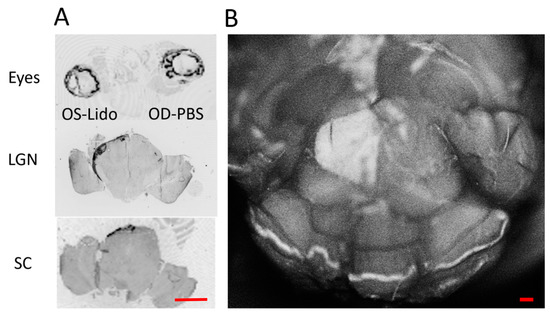

2.1. Retrobulbar Lidocaine Impairs Axon Transport